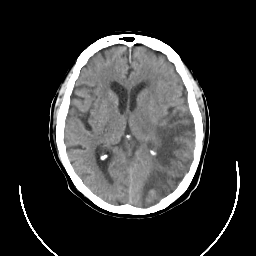

CT Study #3 -- Slice #14

[Home][Help][Clinical][Tour 1] Slice 14